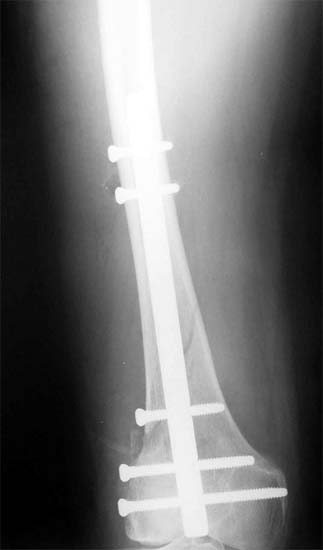

股骨远端骨折是指股骨下端15cm以内的骨折。随着交通运输和工农业的发展,由高能量暴力造成的该部为骨折有增多的趋势,而且伤情复杂,并发症多、致残率高,是难治的骨折之一。股骨远端骨折多位与髓腔狭窄不易下,以髓内钉为基础的中心型固定方法更符和股骨的生物力学特点,固定确实,且不破坏骨折短的血运,便于患肢尽早活动,被称为“生物学”内固定技术。可以达到满意的复位,恢复关界面与关节间的正常解剖关系。,采用这种可靠稳妥的固定技术,便于早期进行膝关节的CPM练习,缩短骨折愈合时间,降低骨不愈合率及感染率。最大限度减少膝关节僵硬、粘连及畸形等并发症是治疗的关键所在。

股骨远端粉碎骨折 采用闭合逆行穿钉法,带锁髓内钉内固定